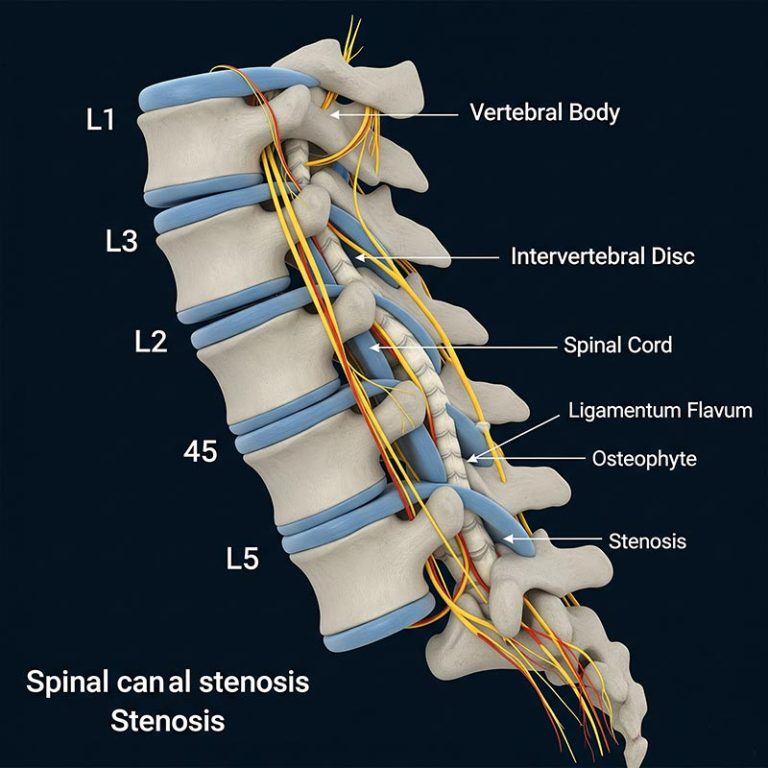

Cervical Spinal Canal Stenosis is a condition where the spinal canal in the neck narrows, putting pressure...

Spinal Canal Stenosis is a condition where the space within the spinal canal narrows, putting pressure...